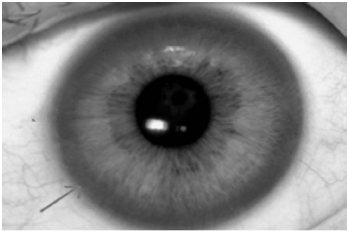

Ao exame: Lúcida, orientada, porém com disartria e disfonia, eupneica em ar ambiente, anictérica, afebril. FC: 64 bpm, PA: 110x60 mmHg, SatO2: 97%. Presença de marcha atáxica, tremor de repouso, dismetria, e um halo marrom-dourado na periferia da córnea e contornando a íris (figura abaixo – seta) em ambos os olhos. MVUA sem ruídos adventícios, ritmo cardíaco regular em 2T sem sopros ou turgência jugular. Fígado palpável a 8 cm do rebordo costal (hepatimetria 14 cm). MMII sem edema.

Avalie as seguintes afirmativas em relação ao diagnóstico mais provável da doença relacionada ao caso:

I. A ceruloplasmina sérica deve estar baixa;

II. Pacientes com a doença apresentam um maior risco de miocardiopatia e insuficiência cardíaca;

III. Alterações eletrocardiográficas são raras e só ocorrem em pacientes idosos.

Está correto apenas o que se afirma em